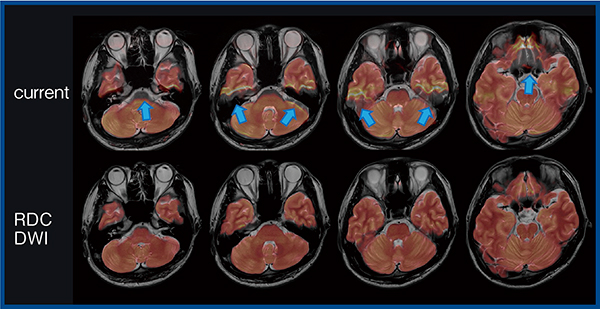

最後に,拡散強調画像(DWI)における歪み低減技術RDC DWIについて紹介する。RDC DWIは,位相エンコード方向が異なる2つの撮像を行い,各画像から歪み量を計算することで歪みを低減した画像を構築する技術である(図5)。RDC DWIはb0画像だけでなく,MPG印加画像においても位相エンコードの異なる撮像を行うことで,磁場不均一性に加え渦電流の影響による歪み補正も行え,より高精度の歪み補正が可能となる。実際の画像でも,RDC DWI適用により頭蓋底の歪みが低減したほか,RDC DWIとT2強調画像のフュージョン画像(図6,7)では,多断面にわたって歪み(↑)が大きく改善した。

図6 RDC DWIとT2強調画像のフュージョン画像(アキシャル像)